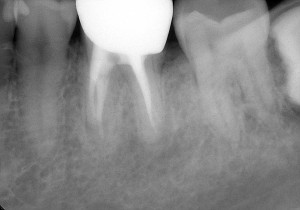

先日、いつもの3ヶ月毎の定期検診にお越しいただき、全体のチェックと共に根管治療部位のレントゲン写真も撮らせていただきました。

この10年症状も無く、もちろん新たなむし歯を作ることなく経過良好で過ごしていただいております。

ここまできて私もホッと一安心といったところです。治療において知識や技術の習得には終わりはありません。私も自分の伸びしろ信じ、多くの患者様に笑顔が戻るように日々精進していきたいと思います。